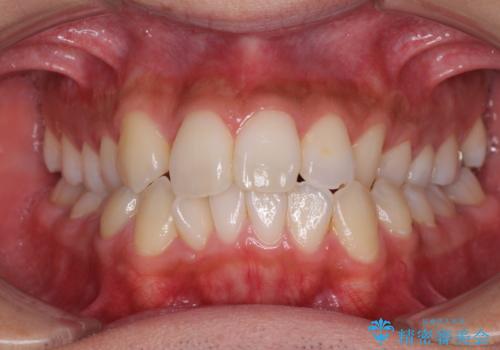

【モニター】左右のクロスバイトをインビザラインできれいに改善

【モニター】八重歯と前歯のクロスバイト ワイヤーを併用しインビザラインで矯正治療